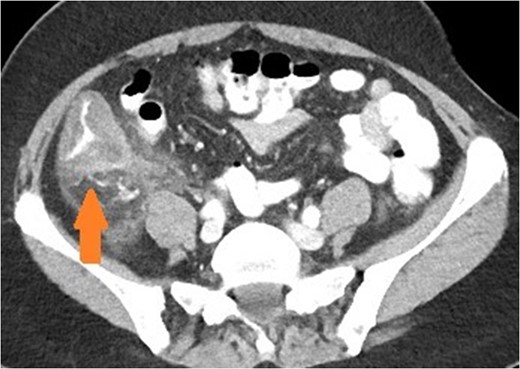

Axial view of patient with caecal carcinoma. Eccentric caecal wall thickening with homogenous contrast enhancement (arrow). Mild pericolic fat stranding is present.

There are a number of CT features that help distinguish bowel wall thickening from malignant and benign causes [3]. A neoplastic cause is suggested if there is focal bowel wall thickening (less than 5 cm of extension) which is typically asymmetrical and eccentric. These may have homogeneous contrast enhancement due to infiltration of a tumour mass, or a heterogeneous areas of low attenuation from ischaemia and necrosis, findings with a sensitivity of up to 97% [4]. Malignancy may also have shouldered edges as opposed to tapering transition to normal bowel wall. Appendiceal dilatation, if present, may be thin walled and without inflammatory stranding due to a gradual obstructive process, although appendicitis can be a presenting symptom for carcinoma. Regional lymphadenopathy and distal metastases, when present, support the diagnosis.